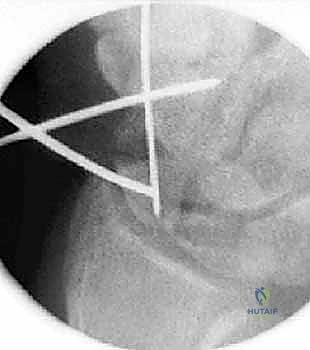

هذه هي التقنية المتقدمة التي يبرع فيها الأستاذ الدكتور محمد هطيف في صنعاء. بدلاً من فتح الرسغ، يتم إجراء العملية بأكملها من خلال شقوق دقيقة لا تتجاوز 2-3 مليمترات، تحت إرشاد جهاز الأشعة المرئية (Fluoroscopy) وبمساعدة المنظار المفصلي الدقيق.

العملية الجراحية بتقنية التدخل المحدود ليست مجرد "إدخال مسمار"، بل هي عمل فني وهندسي دقيق يتطلب مهارة جراحية فائقة، تخطيطاً مسبقاً، وتنسيقاً مثالياً بين يدي الجراح والصور الإشعاعية. يتبع الأستاذ الدكتور محمد هطيف بروتوكولاً صارماً لضمان أعلى معدلات النجاح.